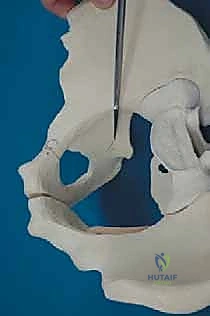

تتميز جراحة PAO عن غيرها من جراحات قطع عظم الحوض القديمة (مثل قطع العظم الثلاثي لـ Steel أو Tonnis) من خلال ميزة ميكانيكية حيوية حاسمة: الحفاظ الدقيق على سلامة العمود الخلفي للحوض (Posterior Column). هذا التمييز التشريحي يقلل من عدم استقرار حلقة الحوض، يسمح للمريض بالحركة المبكرة، ويتيح للجراح إعادة توجيه متعدد المستويات لقطعة الحُق بشكل أكثر قوة ودقة. يتم تحقيق ذلك من خلال تسلسل دقيق للغاية من خمس عمليات قطع عظم (Osteotomies)، كل منها مصمم لتحرير الحُق مع الحفاظ على إمداده الدموي الحيوي.

يكمن سر نجاح جراحة PAO في إجراء خمسة قطوع عظمية منفصلة حول الحُق، لتحريره بالكامل عن باقي الحوض، مع ترك العمود الخلفي سليماً كدعامة أساسية.

القطع الأول: القطع الإسكي غير المكتمل (Incomplete Ischial Osteotomy)

باستخدام إزميل خاص ذو زاوية (Angled Osteotome)، يتم إجراء قطع في عظم الإسك أسفل الحُق مباشرة (في الأخدود تحت الحُقي). يتم هذا القطع بتوجيه الأشعة السينية (Fluoroscopy) لضمان عدم اختراق المفصل. يحرص الدكتور هطيف على إبعاد العصب الوركي والأوعية السدادية بأمان تام.